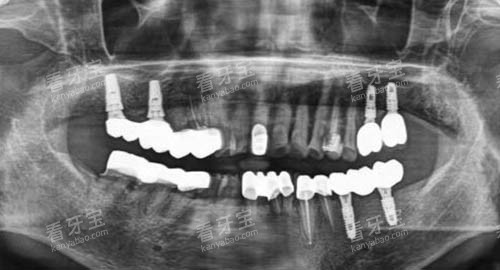

例如,医院的口腔CT设备可以清晰地显示口腔内部的结构,帮助医生更比较准地诊断病情;智能化口腔扫描仪可以快速获取患者口腔的三维模型,为牙齿矫正等治疗提供更好的数据支持。

在特色项目方面,哈尔滨鲸鱼口腔的牙齿矫正和种植牙技术尤为突出。

在种植牙方面,医院引进了国内外可靠的种植系统,由经验充足的医生进行操作,确保种植牙的成功概率和稳定性。